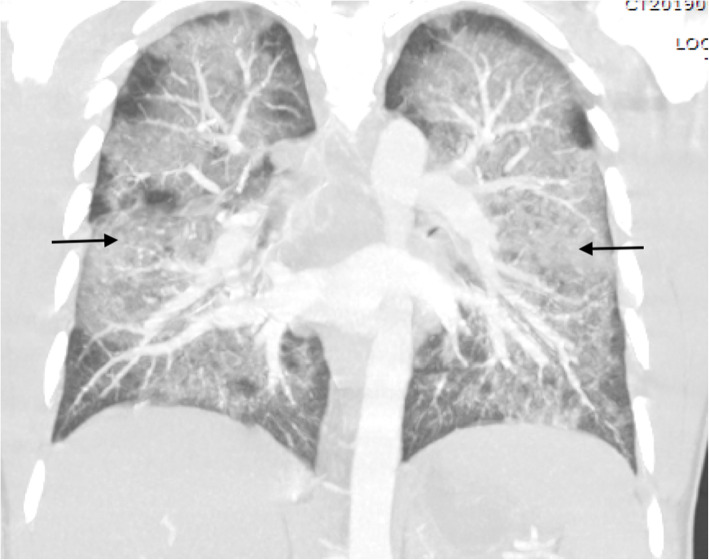

Laboratory studies revealed leukocytosis of 17.0 × 109/L with 93% neutrophils and an elevated lactic acid of 1.9 mmol/L. The findings of the patient’s chemistry panel were unremarkable. His urine drug screen result was positive for cannabinoids and benzodiazepines. His erythrocyte sedimentation rate was slightly elevated at 63 mm/hour. His human immunodeficiency virus and hepatitis B and C virus test results were negative. A viral panel was obtained, which showed positive results for rhinovirus and enterovirus, but otherwise negative findings were reported. This patient’s hospitalization occurred before the coronavirus disease 2019 (COVID-19) pandemic; therefore, no COVID-19 testing was available at the time. He had negative test results for antineutrophil antibodies, cytoplasmic and perinuclear antineutrophil cytoplasmic antibodies, and myeloperoxidase. His echocardiogram demonstrated a left ventricular ejection fraction of 64%; otherwise, he had no effusion, no vegetation, or other acute findings. A plain chest x-ray (CXR) (Fig. 2) demonstrated diffuse central predominant interstitial opacities. A computed tomographic (CT) angiogram of the chest was then obtained (Figs. 3 and 4), which confirmed diffuse bilateral interstitial infiltrates, with no evidence of vascular injury or pulmonary embolism.